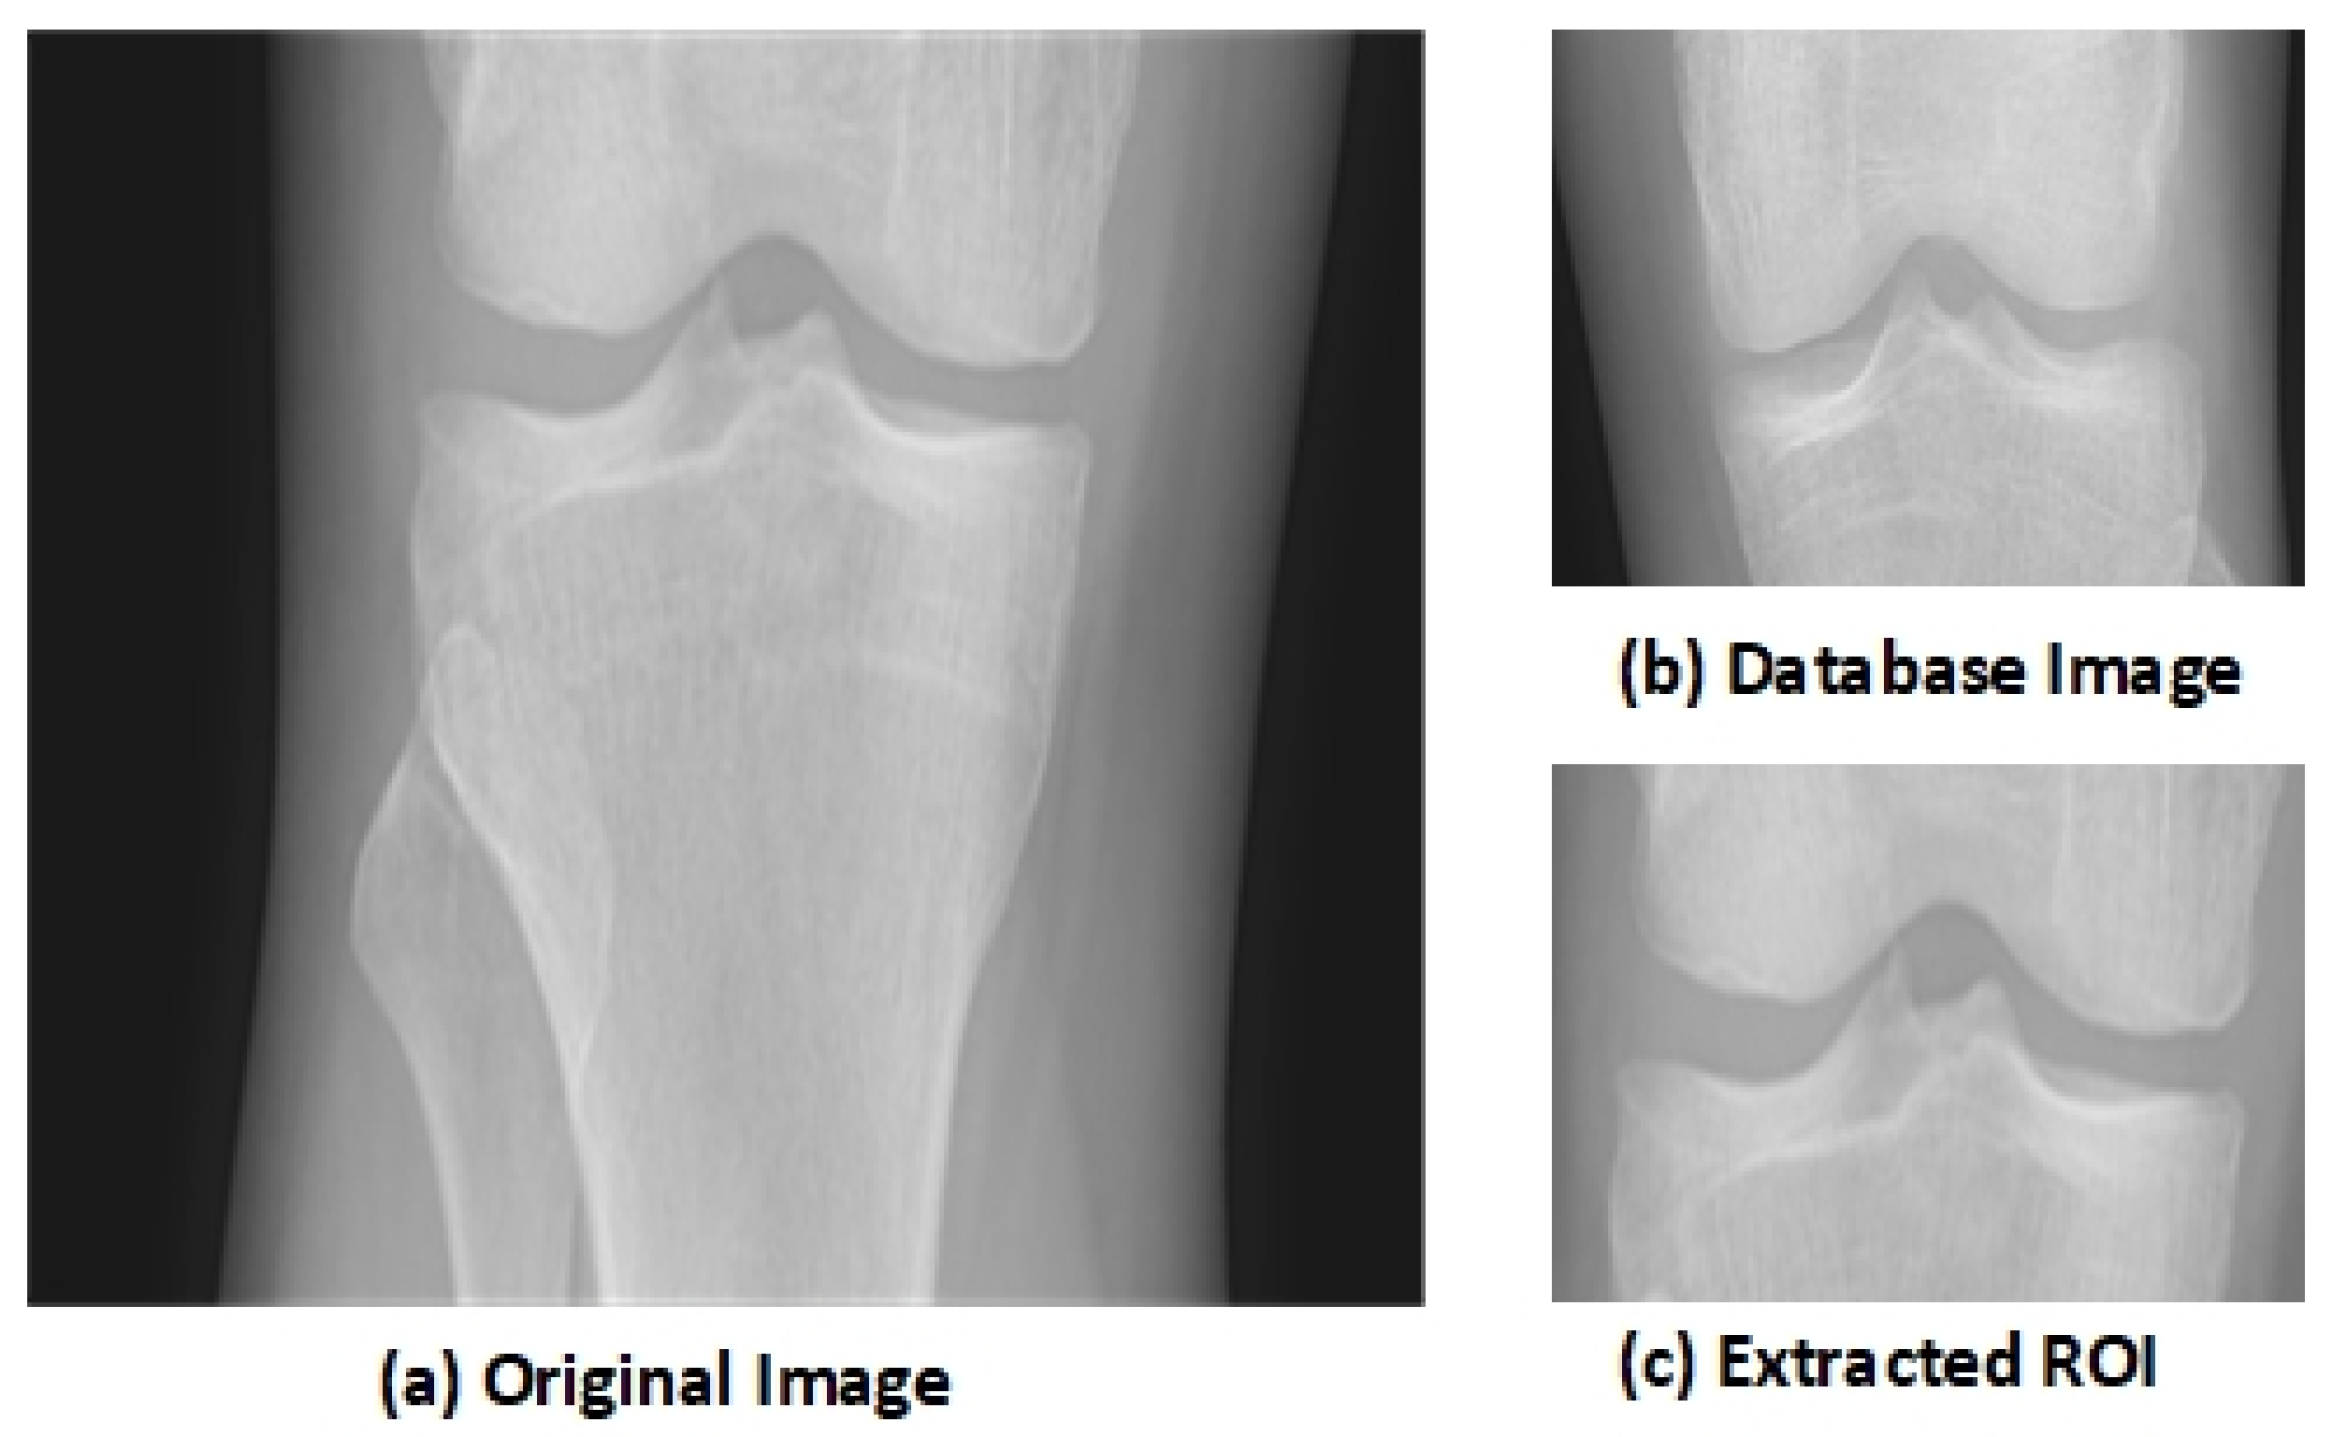

The key aspect of the algorithm is detecting the early KOA disease space width of the knee joint. This disease becomes advanced as the gap between knee joints increases with age. The region of interest (ROI) is the tibiofemoral joint. The ROI is calculated through a matching technique with the database of knee images. The database image moves on the input image pixel by pixel, and the similarity among the image’s blocks through a histogram of gradients’ features is computed. The block, having maximum similarity, is selected as the ROI. This similarity-based mechanism outperforms the traditional algorithms. Let us suppose that an input image I of knee is fed to the system having size I × J, and D represents the database image, having size × , where is the vector of HOG, having a size of 1 × h of the database image D. and is the block of d × that is located at (m,n) in the image I. The HOG feature of is represented as . Mean absolute difference (MAD) is used to compute the similarity among the database image D and the image block

The block with the minimum MAD is selected as the ROI that contains the knee joint. The knee image that is used in the database is shown in Figure 1b. Figure 1a shows the original knee image, while Figure 1c shows the selected ROI. The selected region has essential features as it shows the joint space width (JSW).

Figure 1.

Extraction of Region of Interest (ROI) [48].